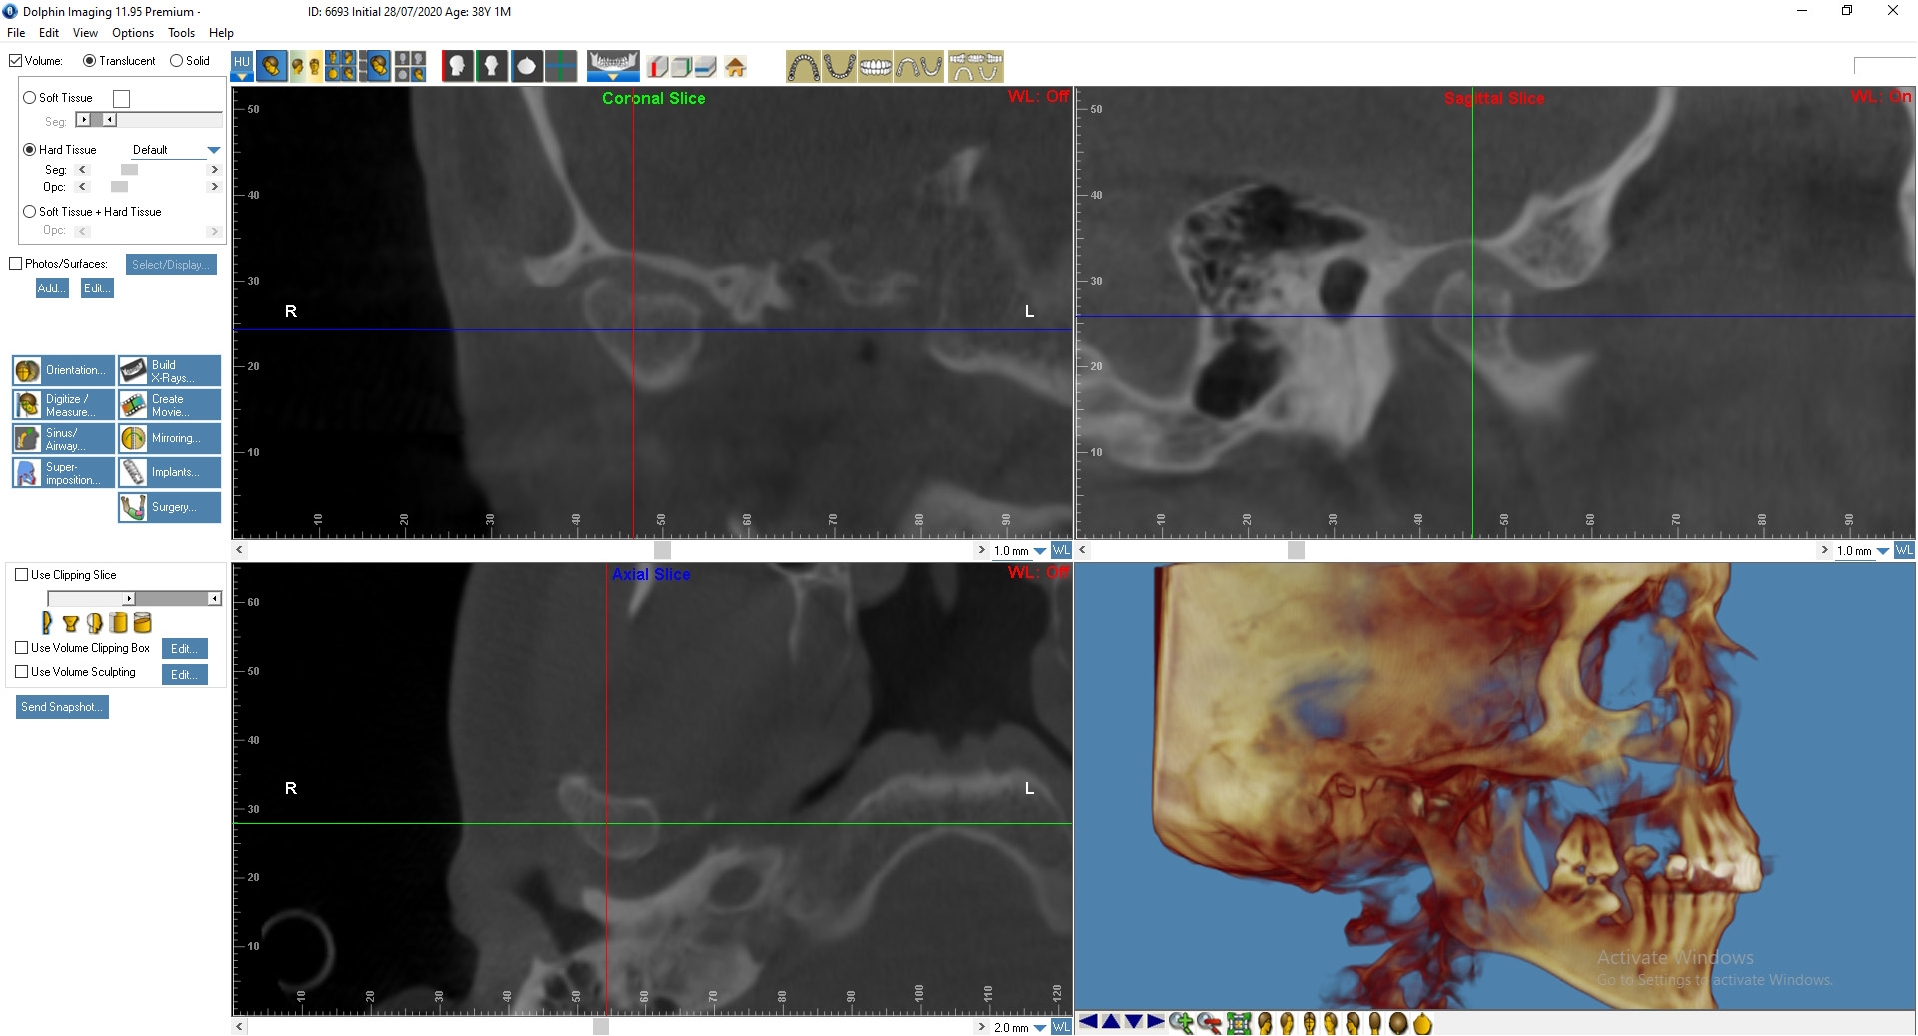

Пациенту была выполнена МРТ ВНЧС.

По данным МРТ: Артроз правого ВНЧ сустава 1-й степени. Полная вентро-латеральная дислокация суставного диска с репозицией. Гипомобильность сустава малой степени выраженности.

Артроз левого ВНЧ сустава 2-й степени, синовит. Полная вентро-латеральная дислокация суставного диска с частичной репозицией. Гипомобильность сустава малой степени выраженности. Начальные признаки фиброза биламинарной структуры.

Лечение: Пациенту Д. была выполнена окклюзиограмма, на основании которой были устранены супраконтакты методом избирательного пришлифовывания зубов. Также было выполнено лечение сплинт-терапией для восстановления работы височно-челюстного сустава. Фиксирована брекет-система на зубы нижней челюсти (рис. 3, 4).

Рис. 4. Пациент Д., 38 лет. КТ ВНЧС до начала лечения